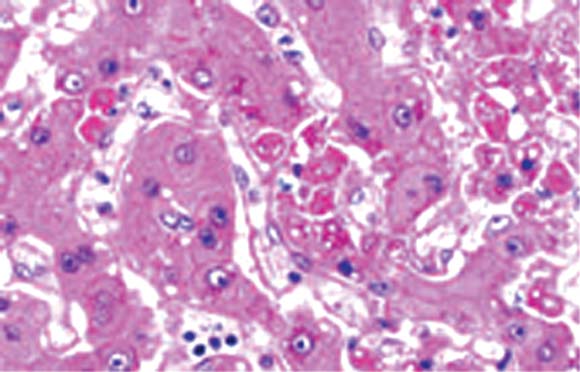

EVDの一般的な症状は、突然の発熱、強い脱力感、筋肉痛、頭痛、喉の痛みなどに始まり、その後、嘔吐、下痢、発疹が出現する。肝機能および腎機能の異常も伴う。さらに症状が増悪すると出血傾向や意識障害が出現する。結膜充血などの急性眼症状は発熱などの他の徴候と併せて特定された場合、EVDの早期診断に寄与する可能性がある。検査所見としては白血球数や血小板数の減少、および肝酵素値の上昇が認められる。潜伏期間は2日から最長3週間といわれており、汚染注射器を通した感染では短く、接触感染では長くなる傾向がある。致命率が90%に達することがある。2000年のウガンダでの流行では上記症状に加えて、衰弱のほか下痢等の消化器症状が目立ち、出血症状が認められたのは約10%であった。肝臓でのウイルス増殖(旧版「エボラ出血熱とは」図3(JPG:33.4 KB )を参照)による肝腫脹により、右季肋部の圧痛や叩打痛が特徴的である。